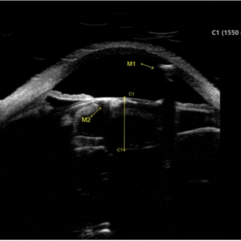

Ultrasound biomicroscopy image of gas in the anterior chamber (A, M1) and lenticular cortex (A, M2) of a 68-year-old man following pneumatic retinopexy. Patient presented with a macula-off retinal detachment requiring vitrectomy, with pneumatic retinopexy done in office at post-operative week 1 to supplement poor gas fill.